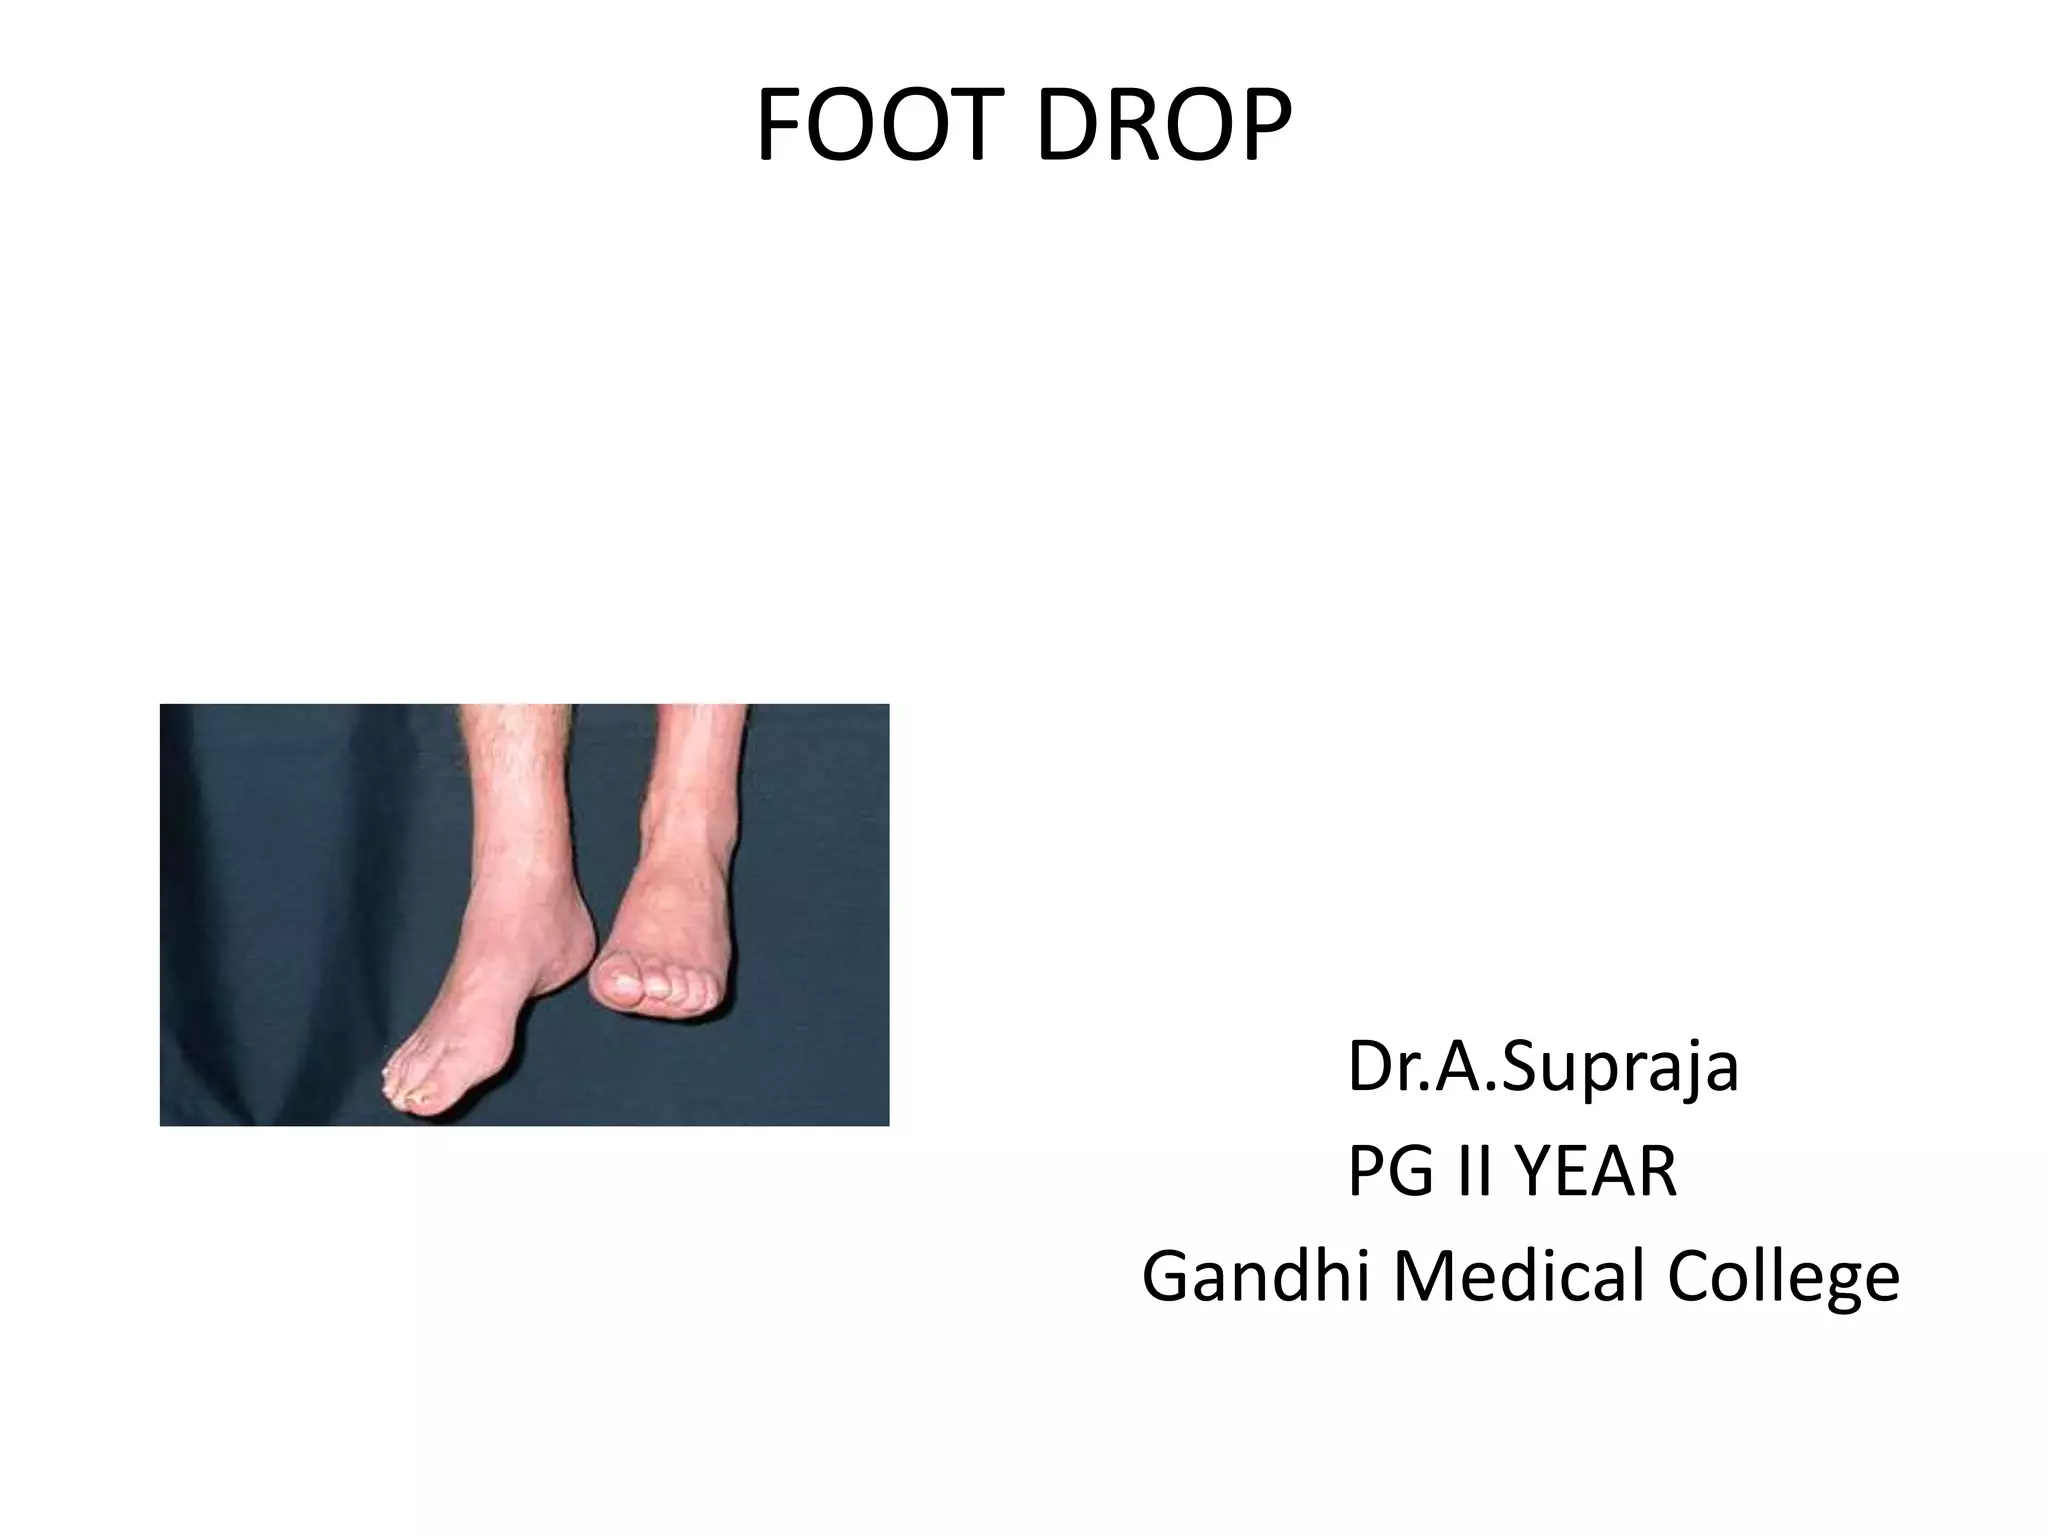

Foot drop is the inability to lift the front part of the foot. It can be caused by injuries or conditions that damage the common peroneal nerve. Symptoms include difficulty lifting the foot and dragging the toes. Treatment depends on the underlying cause but may include bracing, nerve stimulation, tendon transfers, or joint fusions. The goal is to improve mobility and gait.